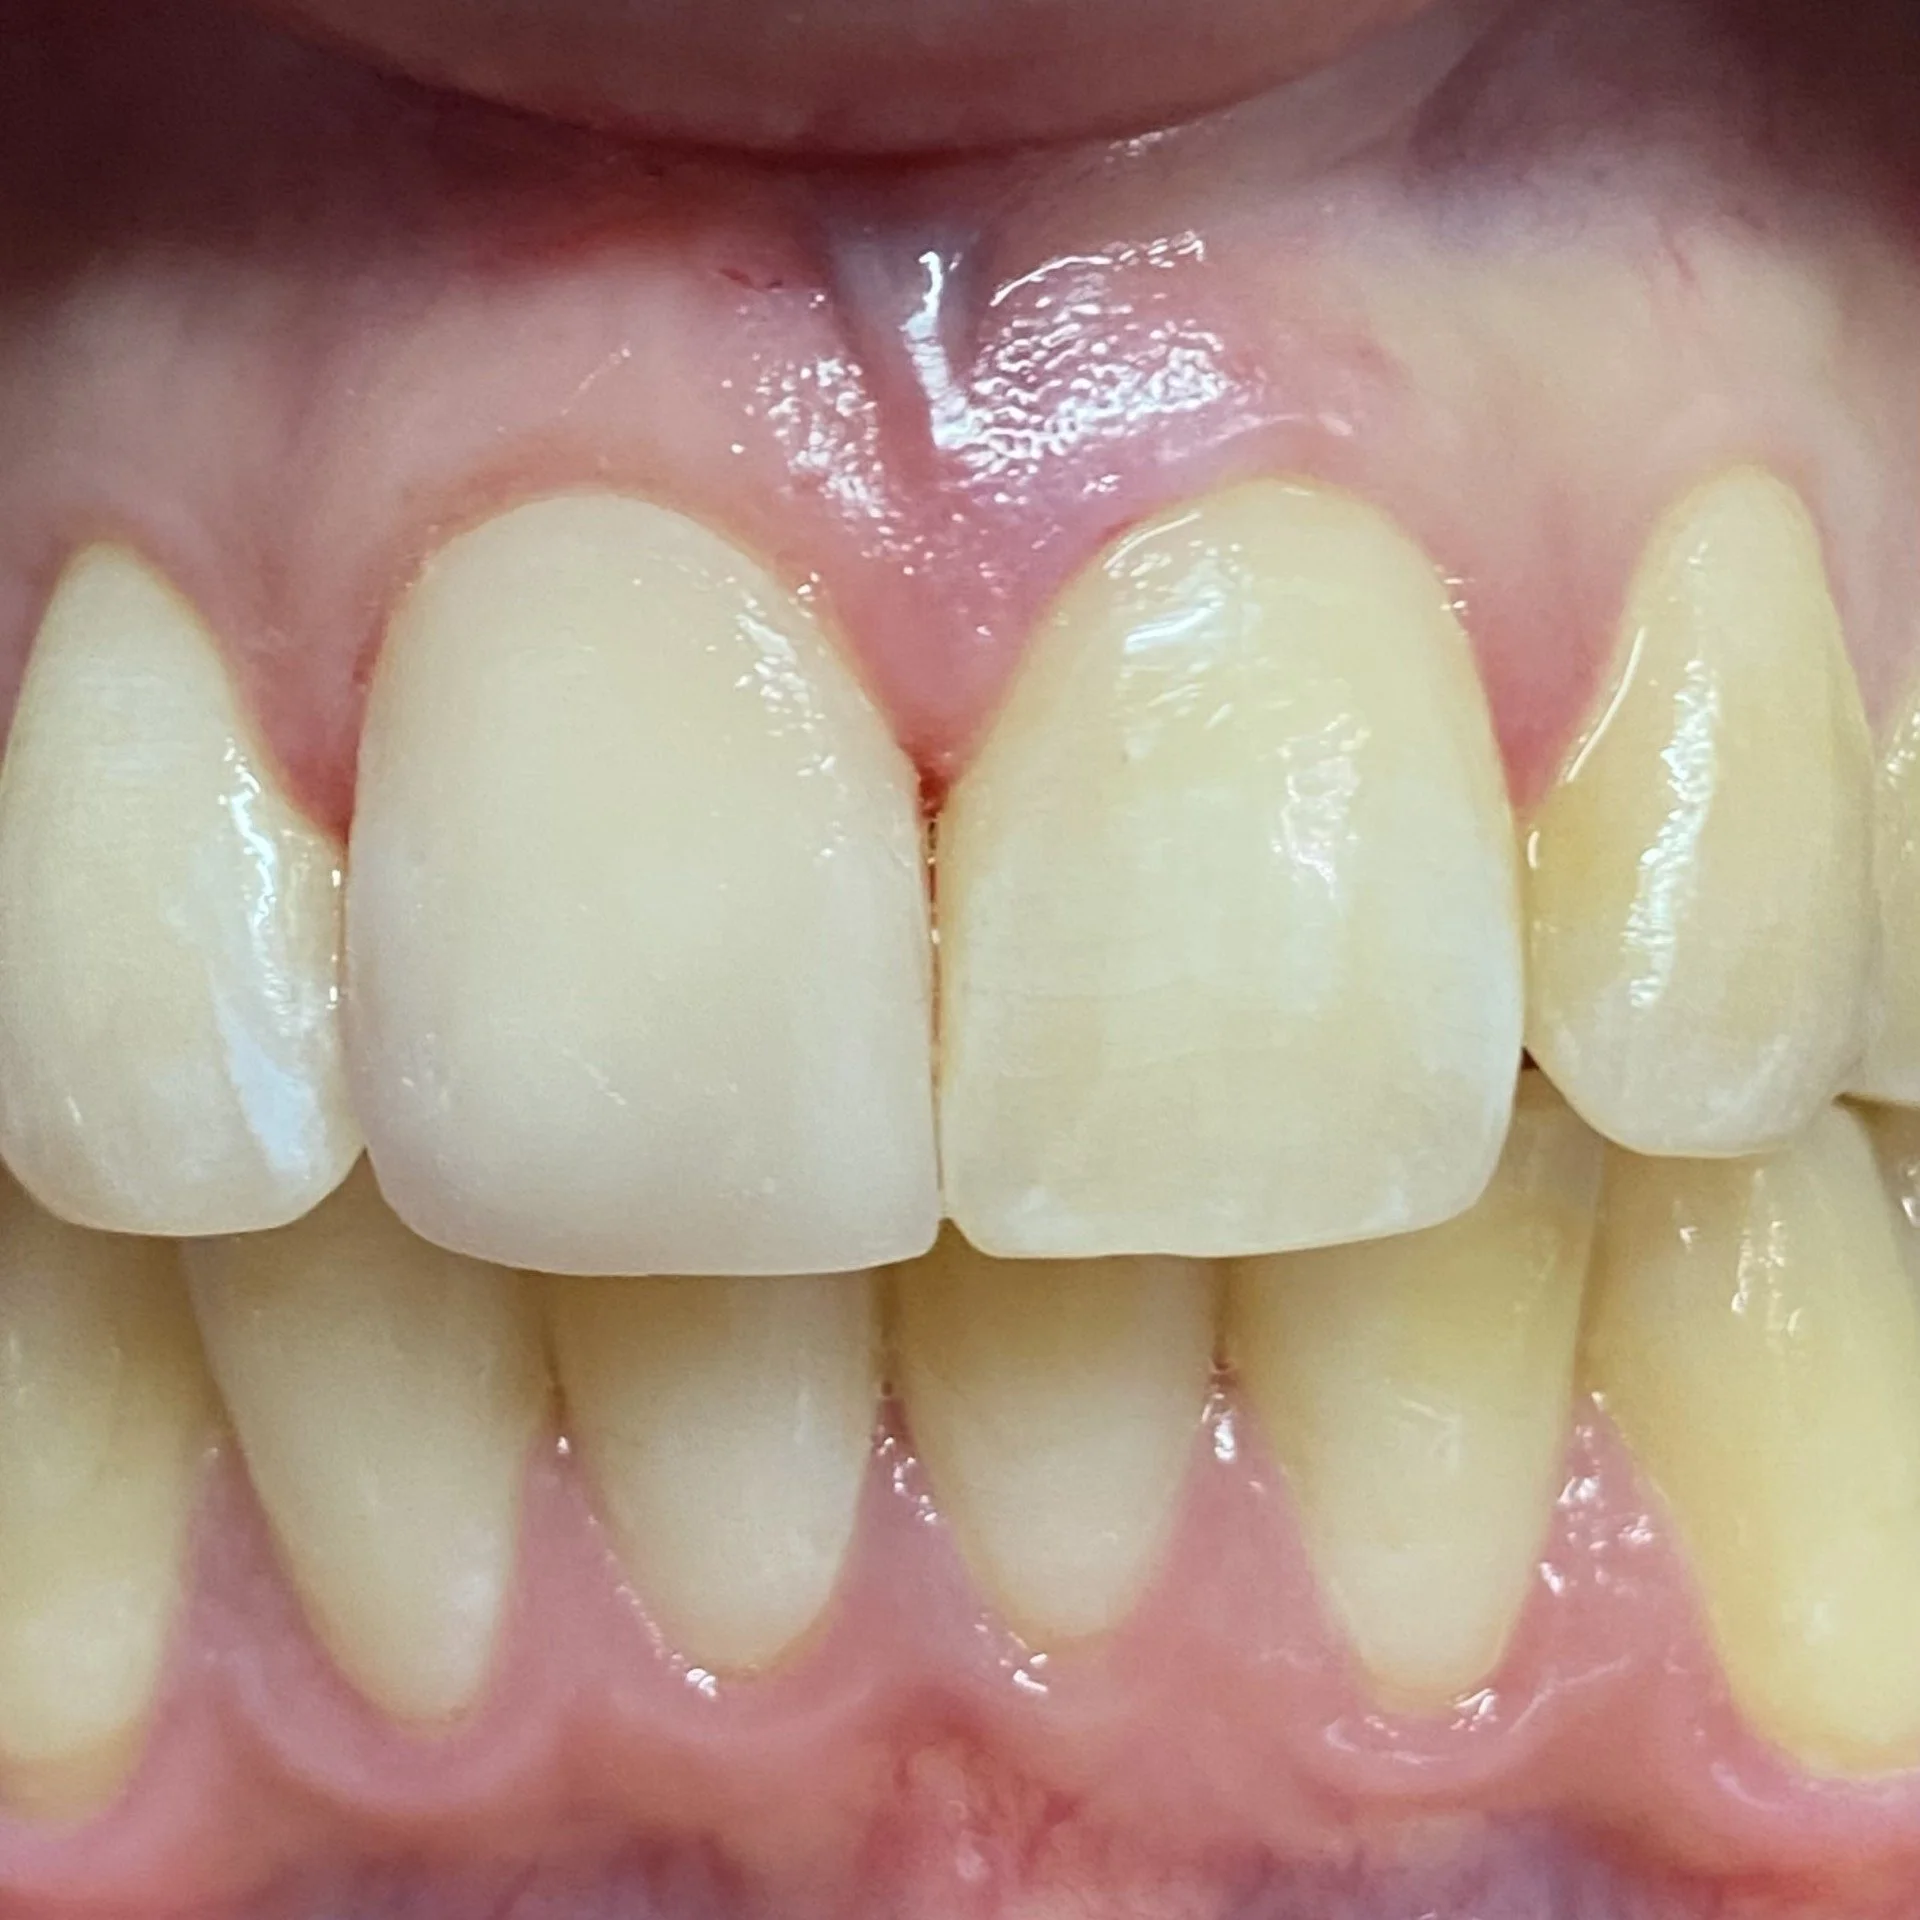

The completed case on the day of fitting and the gum is pale whitish in colour from the local anaesthetic.

-

This is the follow up in 2025